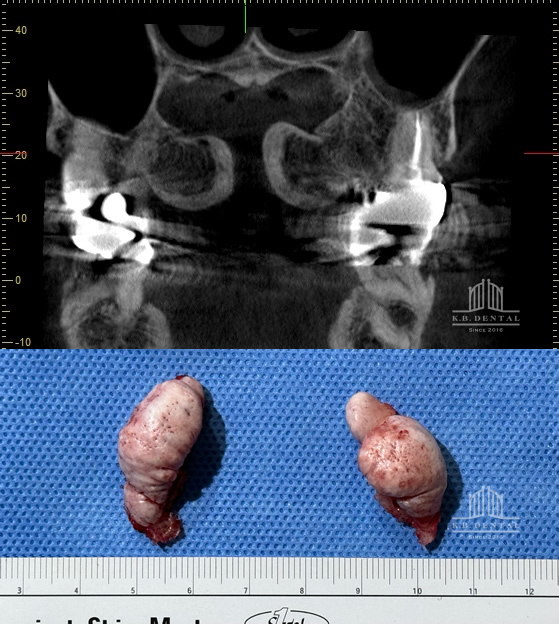

唾石(だせき)

右顎下腺管内の唾石摘出術 症例

唾石(だせき)とは唾液腺にできる結石のことです。当院のケースとしては珍しい手術ですが、このような症状にも外科処置で対応しております。リラックス麻酔による静脈内鎮静下にて摘出術を施行しました。

症状としては、唾腺痛(だせんつう)といって、食事時に唾液が出るときに痛みが出ます。また舌下部の違和感などもあります。当院では唾液腺の分泌障害、唾液腺の痛み・腫れなどでお困りの方のための唾石摘出術を積極的に行っております。